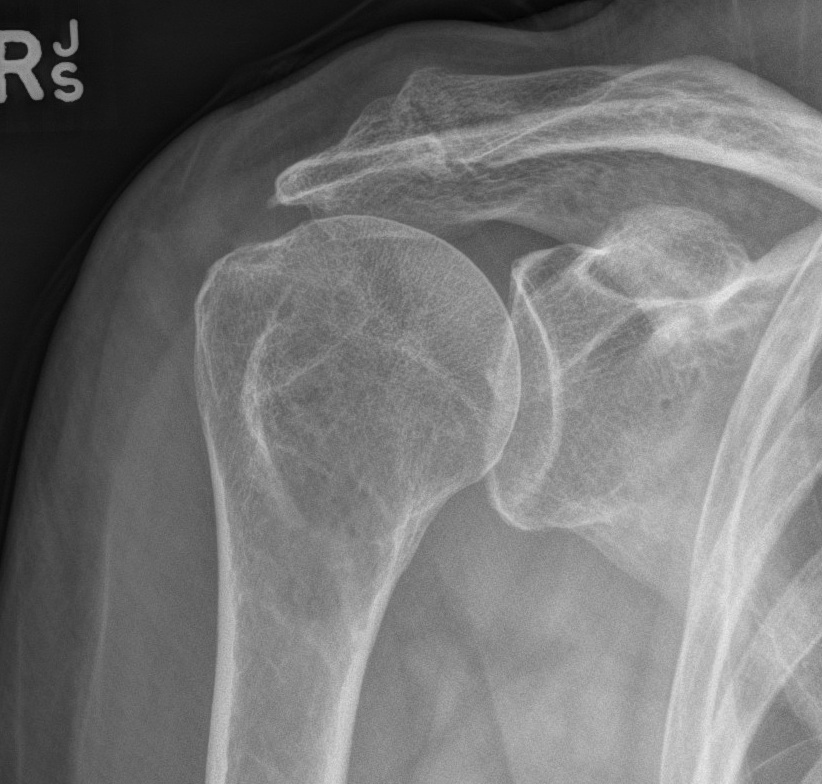

Retear

Presentation

Pain / stiffness / weakness

Incidence

- 1600 arthroscopic RCR

- retear rate 7% with cuff tears < 2 cm2

- retear rate 44% with tears > 8 cm2